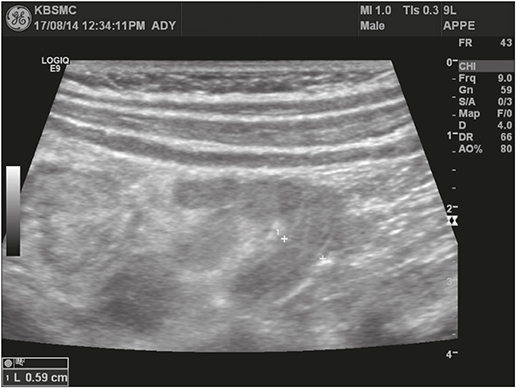

Abdominal radiography showed gaseous distension of the colon (Fig. 1). Laboratory findings included leukocytosis (22.64 k/mm3) with an upper left shift (segment 82.9%), mild anemia (12.5 g/dL), thrombocytosis (456 k/mm3) and decreased serum glucose (65 mg/dL) and sodium (134 mg/dL) levels. Plasma urea and creatinine concentrations, and those of other electrolytes were within normal limits, and C-reactive protein (CRP) was also nearly normal (0.66 mg/dL).

Fig. 1

Simple abdomen radiograph (flat) at the admission.